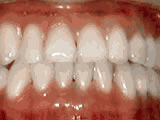

Open bite - Front teeth don't touch

Patient sucked her thumb as a young child. She started treatment at age 13. She had braces and a special appliance — called a crib — to retrain the tongue, for 28 months. Now she can bite the lettuce out of a sandwich.